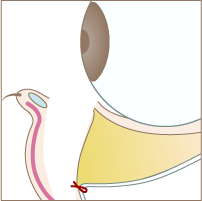

Step 02

脂肪が溜まっている部分の下側の隔膜を切開します。